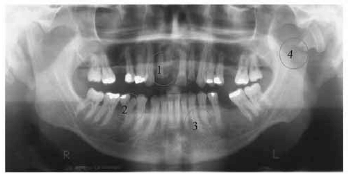

Tendo como referência a imagem radiográfica acima, assinale a opção que apresenta a identificação incorreta.